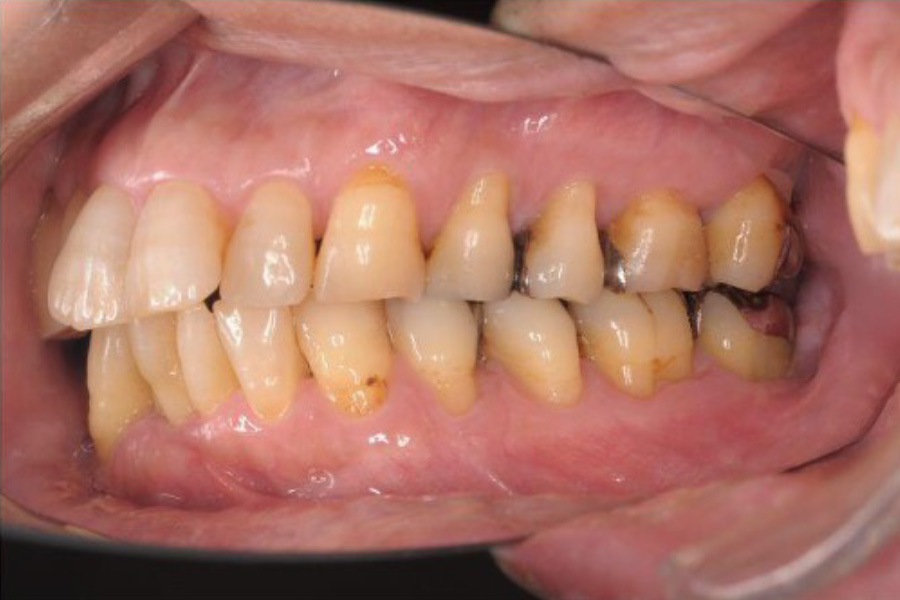

治療前

| 治療内容 | 全顎治療:歯周病治療、抜歯、根管治療、 咬合治療・矯正治療、フルメタルクラウン(保険) |